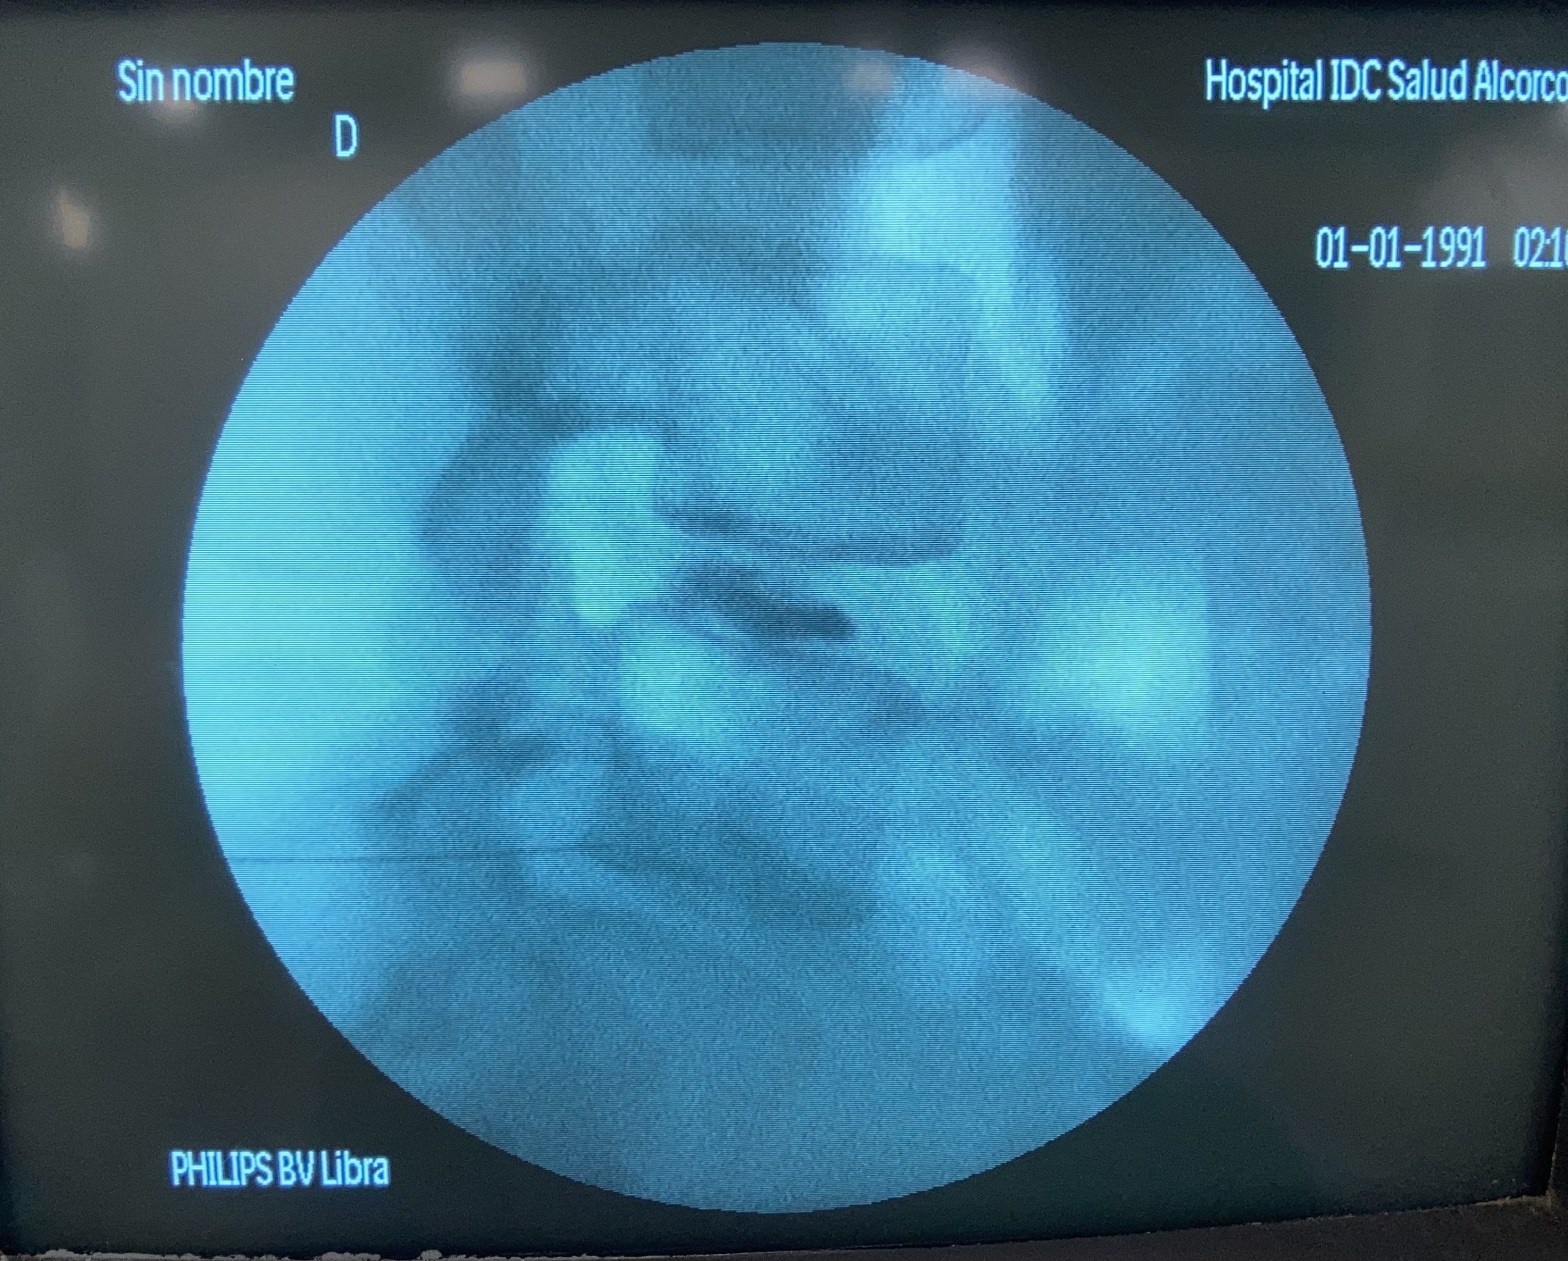

Aplastamiento vertebral

La columna vertebral, denominada así en clara referencia a las estructuras arquitectónicas que soportan los edificios, las creencias y la cultura, es una estructura muy compleja…